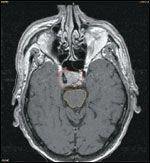

In late 2004, the patient developed progressive headaches without associated symptomatology and underwent an MRI of the brain at our institution. The MRI demonstrated a hypervascular suprasellar mass measuring 2.0 cm in greatest dimension, involving the right cavernous sinus, adjacent pituitary fossa, and medial right petrous bone. No other lesions were identified on this MRI or on the follow-up CT scans of the thorax, abdomen, and pelvis.

FIGURE 1

Brain MRI

The case was reviewed by a multidisciplinary tumor board, at which it was decided that surgical resection was not feasible and tissue diagnosis would carry a high risk of potentially fatal hemorrhage. The patient then received intensity-modulated radiation therapy (IMRT) to this lesion, utilizing 6 MV photons at 180 cGy per fraction to a total dose of 5,040 cGy to the 90% isodose line in 37 elapsed days (Figure 1). This protracted IMRT regimen was chosen to minimize neurotoxicity, as the treatment field potentially overlapped the previous cervical field treated 10 years prior. Unfortunately, the patient developed midthoracic spine pain during the course of IMRT.